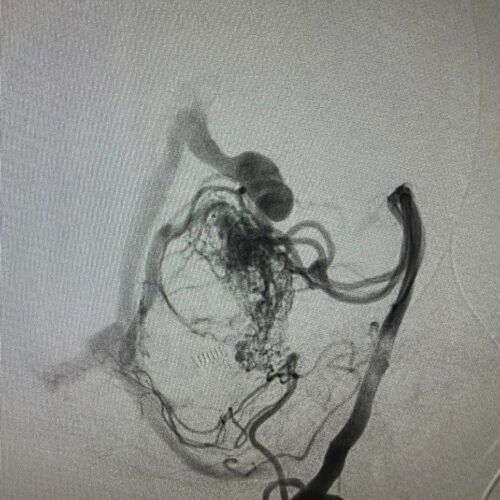

Δια ζώσης συμμετοχή των φοιτητών του Πανεπιστημίου Πατρών σε εξειδικευμένες τεχνικές ενδοαγγειακής αντιμετώπισης αγγειακών δυσπλασιών του κεντρικού νευρικού συστήματος.

Στην επέμβαση συμμετείχαν ο Καθηγητής Ενδοαγγειακής Νευροχειρουργικής Κος Β. Παναγιωτόπουλος, ο Καθηγητής Επεμβατικής Νευροακτινολογίας κος Π. Ζαμπάκης, ο επιμελητής επεμβατικής ακτινολογίας κος Μ. Θεοφάνης και ο αναισθησιολόγος κ. Γούδας.